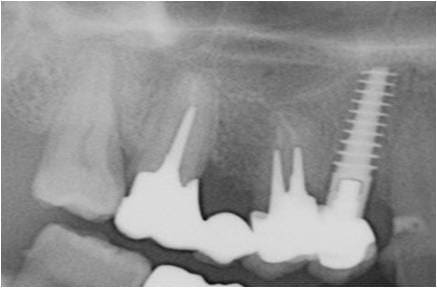

étude du scan et plutôt que les forets, ostéotomes (manuels, impactés) et ou spreader (messinger, MIS, ou autres) la corticale du sinus se sens en général et tu pourras la longer sans effraction (encore que dans ce cas, ça s’appelle un Summers et ça marche fort bien.

exemple un D2 Tatum posé en 90 (à l'époque pas de scann...donc reflexion sur le pano et visualisation 3 D dans la tête...surtout dans celle du patient.

la photo est de 2012